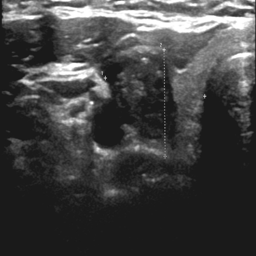

Thyroid nodule segmentation in the ultrasound image is critical for accurate thyroid disease diagnosis Tessler et al. (2017); Chen et al. (2020), but suffers from the blurred structures of anatomy with speckle noise, making it highly dependent on the expertise of the radiologist Khor et al. (2022). Employing deep learning algorithms Chen et al. (2022); Chi et al. (2023); Ozcan et al. (2024); Xiang et al. (2025) for thyroid nodule segmentation can significantly enhance diagnostic efficiency for healthcare professionals. While fully supervised algorithms Ronneberger et al. (2015); Cai et al. (2020); Zheng et al. (2021); Cao et al. (2023); Tao et al. (2022) achieve promising performance on specific datasets where precise ground truth masks are available for training, acquiring a large number of delicate annotations remains resource-intensive and time-consuming Liu et al. (2024).

For thyroid nodule segmentation, weak supervision has been considered as a trend with various promising models have been proposed. However, due to the quality of ultrasound images and the morphological variability of nodules, applying weak supervision to thyroid nodule segmentation in ultrasound images still faced two issues: pseudo-label noise and irrational learning strategies.